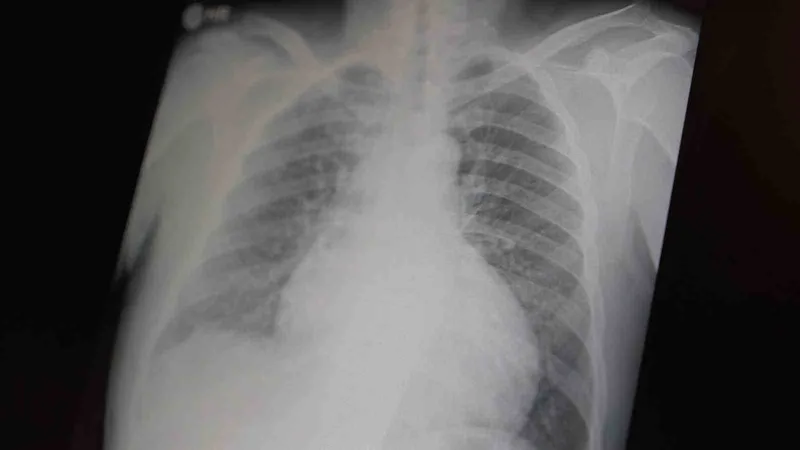

Prof. Dr. Şevket Özkaya, çocukları ve gençleri etkileyen bağımlılıklar hakkında açıklamalarda bulundu. Metamfetaminin sentetik bir uyuşturucu olduğunu ve kullanımının ölümcül sonuçlar doğurduğunu ifade eden Özkaya, "Tüm dünyada çocukları ve gençleri etkileyen iki önemli bağımlılıktan bahsetmek istiyorum. Bunlar metamfetamin ve kokain bağımlılığıdır. Metamfetamin en ölümcül, en çok bağımlılık yapan, okul çağında en kolay ulaşılabilen bir sentetik uyuşturucudur. Kullanıma bağlı ciddi akciğer ve karaciğer sorunları ortaya çıkıyor. Çok küçük dozlarda bile anında bağımlılık yapabiliyor ve tedaviyle bırakılması çok zor bir bağımlılıktır" dedi.

Açıklamalarında, her iki uyuşturucunun beyin hasarı oluşturduğunu ve nöro sinir hücrelerini harap ederek solunum ve kalbin durmasına sebep olduğunu vurgulayan Özkaya, "Metamfetamin tüm dünyada bir sorun olmanın ötesinde, ülkemizde de gençlerimizi etkileyen toplumsal bir sorun olarak görülmelidir" ifadelerini kullandı.